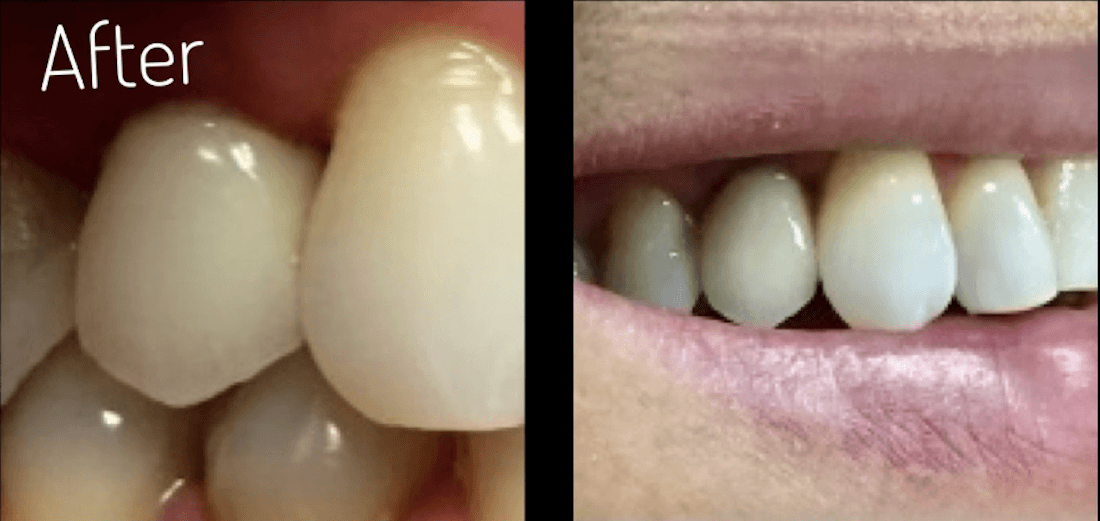

Experience the transformative power of dental implants at its finest. Our precision placement and advanced techniques ensure that each dental implant seamlessly integrates with your natural smile, providing a permanent and reliable solution for missing teeth.

Whether it's a single tooth or multiple teeth, our expertise in dental implants can restore your smile and boost your confidence, allowing you to enjoy life to the fullest.